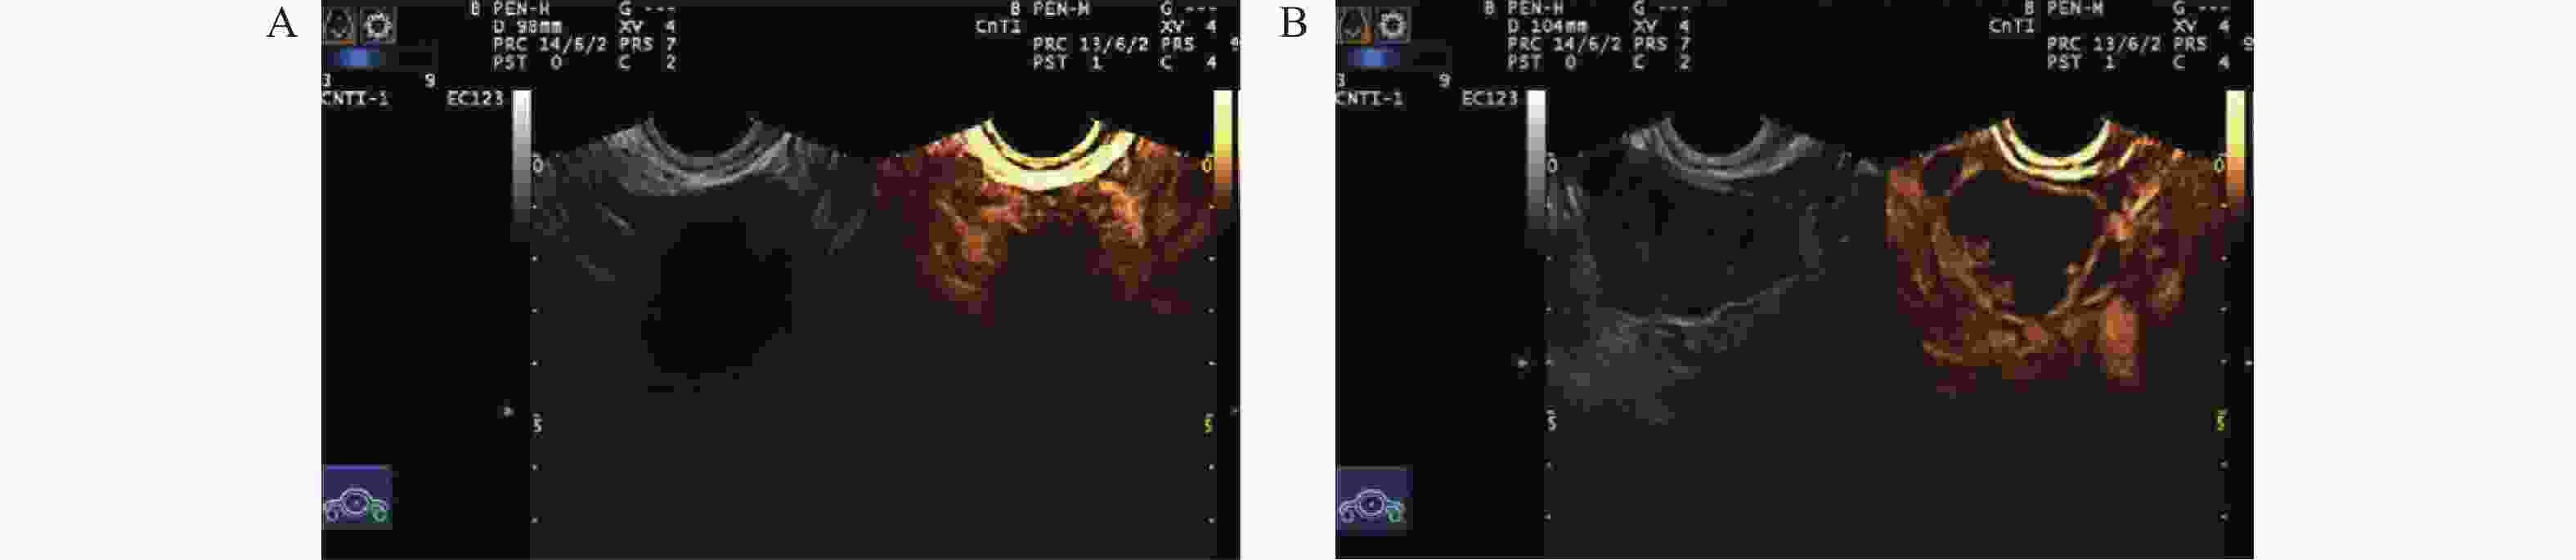

目的 探究超声联合血清白细胞介素-1β(interleukin-1β,IL-1β)、C角蛋白19片段抗原21-1(cytokeratin 19 fragment antigen 21-1,CYFRA21-1)对卵巢癌的诊断价值。 方法 于2020年7月至2023年7月选取沧州中西医结合医院收治的卵巢肿瘤患者250例,经病理检测确诊为卵巢癌的患者114例即为卵巢癌组,从136例良性肿瘤患者中随机选择114例卵巢良性病变患者即为对照组。采用彩色超声诊断仪对所有研究对象进行诊断。采用酶联免疫吸附(enzyme linked immunosorbent assay,ELISA)法检测血清中IL-1β、CYFRA21-1水平。Kappa检验分析诊断方法与手术病理结果的一致性。多因素Logistic回归分析卵巢癌发生影响因素。受试者工作特征(receiver operating characteristic,ROC)曲线分析超声联合血清IL-1β、CYFRA21-1对卵巢癌的诊断价值。 结果 卵巢癌组患者血清中IL-1β、CYFRA21-1水平与对照组相比显著升高(P < 0.05)。与透明细胞癌相比,粘液性腺癌和浆液性腺癌患者血清中IL-1β、CYFRA21-1水平依次显著升高(P < 0.05)。卵巢癌患者血清中IL-1β、CYFRA21-1水平在Ⅰ期<Ⅱ期<Ⅲ期<Ⅳ期(P < 0.05)。血清IL-1β、CYFRA21-1水平升高是卵巢癌发生的危险因素(P < 0.05)。超声联合血清IL-1β、CYFRA21-1对卵巢癌诊断的曲线下面积(area under the curve,AUC)显著高于单一指标诊断的AUC值(Z超声~超声+IL-1β+CYFRA21-1=3.782,P < 0.001;ZIL-1β~超声+IL-1β+CYFRA21-1=4.046,P < 0.001;ZCYFRA21-1~超声+IL-1β+CYFRA21-1=7.279,P < 0.001)。以病理检查结果为依据,联合诊断的一致性(Kappa值=0.789)高于超声(Kappa值=0.658)单独诊断。 结论 超声联合血清IL-1β、CYFRA21-1对卵巢癌的诊断效能较高。 -

Abstract:Objective To explore the diagnostic value of ultrasound combined with serum interleukin-1β (IL-1β) and cytokeratin 19 fragment antigen 21-1 (CYFRA21-1) in ovarian cancer. Methods From July 2020 to July 2023, 250 patients with ovarian tumors admitted to Cangzhou Integrated Chinese and Western Medicine Hospital were enrolled. Among them, 114 patients confirmed as having ovarian cancer by pathological examination comprised the ovarian cancer group. Additionally, 114 patients were randomly selected from the remaining 136 patients with benign tumors to form the control group. All study subjects underwent diagnosis using color ultrasound diagnostic equipment. Serum levels of IL-1β and CYFRA21-1 were detected using the enzyme linked immunosorbent assay (ELISA) method. Kappa test was used to analyze the consistency between diagnostic methods and surgical pathological results. Multivariate logistic regression analysis was performed to identify risk factors for ovarian cancer occurrence. Receiver operating characteristic (ROC) curve analysis was used to evaluate the diagnostic value of ultrasound combined with serum IL-1β and CYFRA21-1 for ovarian cancer. Results Serum levels of IL-1β and CYFRA21-1 in the ovarian cancer group were significantly elevated compared to the control group (P < 0.05). Compared with clear cell carcinoma, serum levels of IL-1β and CYFRA21-1 in patients with mucinous adenocarcinoma and serous adenocarcinoma were significantly elevated (P < 0.05). Serum levels of IL-1β and CYFRA21-1 in ovarian cancer patients showed a progressive increase across stages I<stage II<stage III<stage IV (P < 0.05). Elevated serum levels of IL-1 β and CYFRA21-1 were risk factors for ovarian cancer (P < 0.05). The area under the curve (AUC) for the combined ultrasound with serum IL-1β and CYFRA21-1 in diagnosing ovarian cancer was significantly higher than the AUC values of single-indicator diagnosis (Zultrasound~ultrasound+IL-1β+CYFRA21-1=3.782, P < 0.001; ZIL-1β~ultrasound+IL-1β+CYFRA21-1=4.046, P < 0.001; ZCYFRA21-1~ultrasound+IL-1β+CYFRA21-1=7.279, P < 0.001). Based on pathological examination results, the consistency of combined diagnosis (Kappa value=0.789) was higher than ultrasound alone (Kappa value=0.658). Conclusion The combined diagnostic approach of ultrasound with serum IL-1β and CYFRA21-1 demonstrates high diagnostic efficacy for ovarian cancer. -